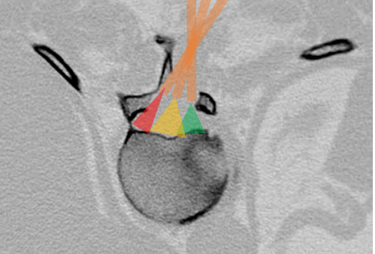

Advanced pain management procedures like Cervical Epidural Injections and Nerve Root Blocks provide significant relief from chronic neck, arm, and back pain caused by disc prolapse or nerve compression. These minimally invasive procedures reduce inflammation around the affected nerves, helping patients avoid or delay surgery while improving mobility and comfort. Under the expertise of Dr. Rohit Thaker, Consultant Endoscopic and Minimally Invasive Spine Surgeon, such procedures are performed with precision and safety.